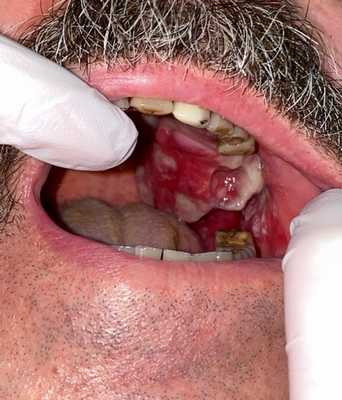

Примеры сарком мягких тканей головы и шеи

Остеогенная саркома альвеолярного отростка верхней челюсти

Остеогенная саркома нижней челюсти

Плеоморфная саркома мягких тканей шеи справа